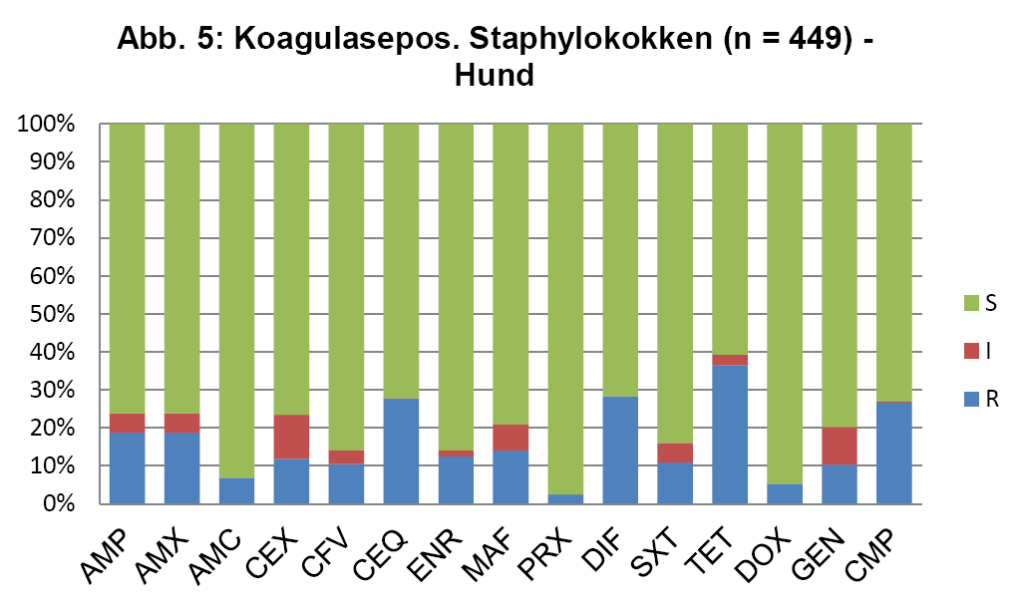

- Abb. 5: Koagulasepos. Staphylokokken (n = 449) – Hund

Abb. 5 zeigt die koagulasepositiven Staphylokokken vom Hund, die Daten für die koagulasenegativen Staphylokokken der Katze sind ähnlich. Die seltener bei der Katze nachgewiesenen koaglulasepositiven Staphylokokken sind etwas resistenter. Abb. 6 zeigt die Enterokokken bei der Katze.

Für die Ersttherapie werden nach ISCAID Richtlinien AMX und SXT vorgeschlagen, wobei AMX der Vorzug gegeben wird. In vielen europäischen Ländern ist AMX sehr gut wirksam gegen E. coli. Dies ist offensichtlich bei uns nicht der Fall (s. Abb. 4). Bei unklarer Keimzusammensetzung wäre daher SXT nach unserer Datenlage für die Ersttherapie der Vorzug zu geben. Auf ENR sollte zunächst aus den oben genannten Gründen verzichtet werden. Es wird noch als Reserveantibiotikum für wirklich schwierige Infektionen benötigt. Wenn im Harnsediment eine Unterscheidung in Kokken und Stäbchen erfolgt, kann man bei Vorliegen von Kokken gut mit AMX als Ersttherapie arbeiten (s. Abb. 5 + 6). Es muss bedacht werden, dass die uns vorliegenden Daten die eigentliche Resistenzlage zu hoch wiedergeben könnten, da häufig erst bei Therapieversagen eine BU eingeleitet wird. Somit könnte die Resistenzlage für AMX in der Praxis besser sein, als hier dargestellt. Darüber hinaus reichert sich AMX im Urin stark an.